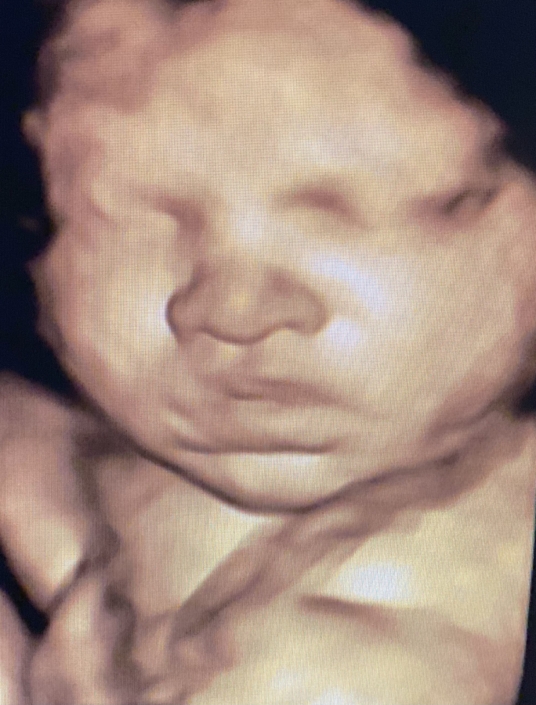

Prenatal Peek®

Prenatal Peek is the leader in 3D 4D Ultrasound. We employ only Certified / Registered Sonographers maintaining unsurpassed standards in 3D ultrasound. You deserve the best! Call us today.